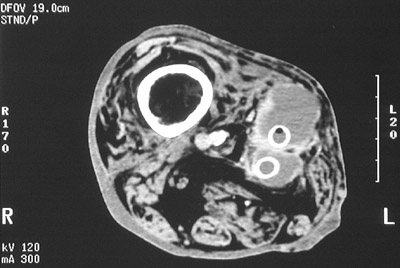

In this diabetic patient with severe peripheral vascular disease, there are two femoral-popliteal PTFE grafts with thrombosis and surrounding fluid collection.